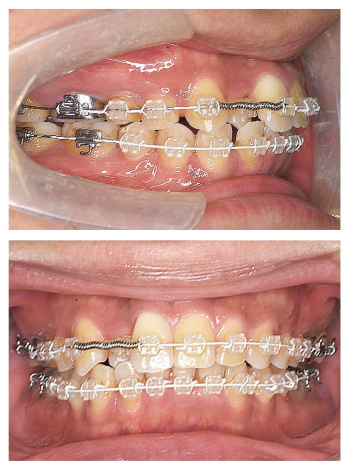

118回 A-58

矯正歯科治療中の口腔内写真(別冊No. 15)を別に示す。

上顎右側犬歯根尖部の歯周組織に生じる生体反応の組合せで正しいのはどれか。2 つ選べ。

解答:b e

解説:

上顎右側3番をオープンコイルで遠心に移動しようとしている。普通、傾斜移動。3番の歯体移動は難しすぎる!もっと強い力がいる。

傾斜移動なので歯冠は遠心移動、歯根は近心移動。なので歯根の近心側は圧迫され、遠心側は牽引側。

圧迫側:骨吸収、破骨細胞、圧迫されるので貧血=血流悪い

牽引側:骨添加、セメント芽細胞、骨芽細胞など作られる方向の細胞、血流良い